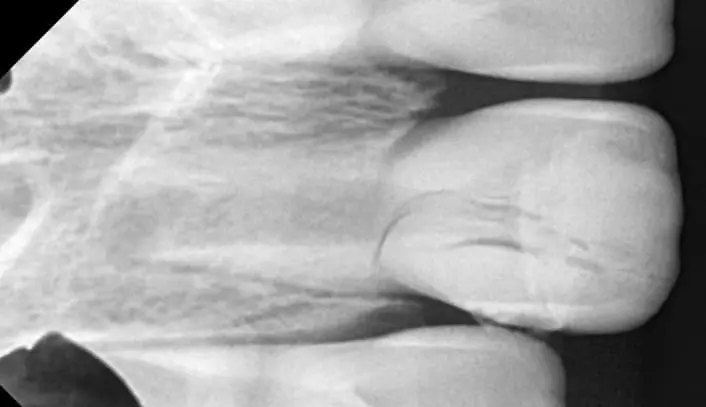

Коли лікар-стоматолог стикається з травмою постійного зуба у дитини, часто необхідно мобілізувати максимум знань і навиків: від реставрації до хірургії. Але найперше - це правильно визначити тактику. Наш курс допоможе відповідним чином приймати рішення в різних клінічних випадках травми постійних зубів у дітей. І не тільки приймати рішення, а і належно їх реалізувати в лікувальну тактику. На детальних клінічних прикладах ми демонструємо належну клінічну тактику та техніки, які часто допомагають врятувати постійні зуби юних пацієнтів.